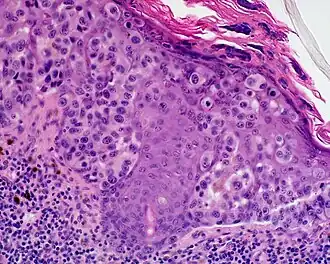

L'aspect anatomo-pathologique est pour la composante intradermique celui d'une prolifération lentigineuse longeant les annexes pilo-sébacées, dont la densité et les atypies augmentent en fonction de l'ancienneté. Des thèques et une ascension pagétoïde peuvent apparaître. Quand vient la composante dermique l'aspect est celui d'un nodule fusocellulaire avec mitoses peu nombreuses[6].